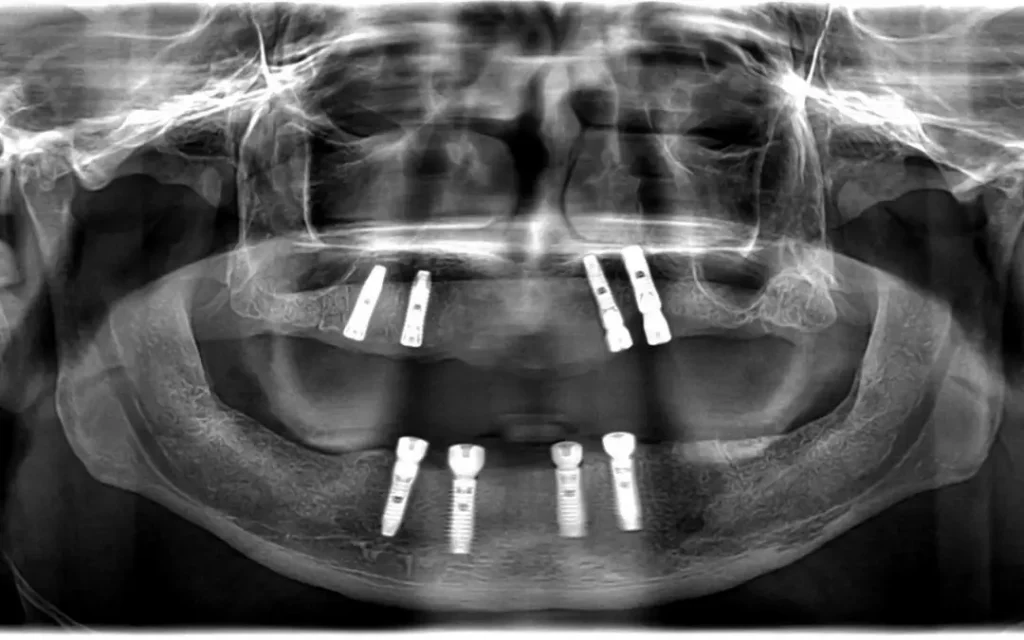

All-on-4 implant tedavisi, tüm dişlerinizi tek seans içerisinde çıkartılıp yerine 4 adet implant üzerine sabitlenen bir köprü ile değiştirmektir. Bu tedavi yöntemi, diş eksiklikleri olan kişilere daha hızlı ve daha kolay bir diş restorasyonu sağlar.

All-on-4 implant tedavisi, bir cerrahi işlemle yapılır. Tedavi sırasında, öncelikle diş etleri kaldırılır ve dişler çekilir. Sonrasında, implantlar çene kemiğine yerleştirilir ve geçici bir köprü takılır. Yerleştirilen implantlar iyileşme sürecinde kemikle kaynaşır ve kalıcı köprü yerleştirilir.

All-on-4 implant tedavisi, hastanın durumuna bağlı olarak değişebilir. İmplantların yerleştirilmesi birkaç saat sürebilirken iyileşme süreci 3-6 ay arasında değişebilir. Tedavi süreci tamamlanana kadar geçici bir köprü takılır.